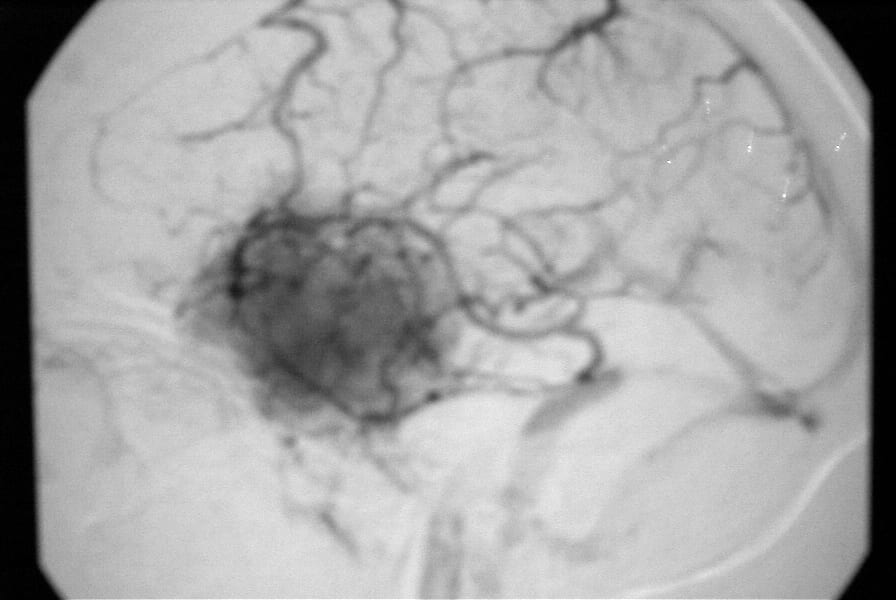

El diagnóstico se puede confirmar y el tumor localizar mediante:

• Angiografía cerebral